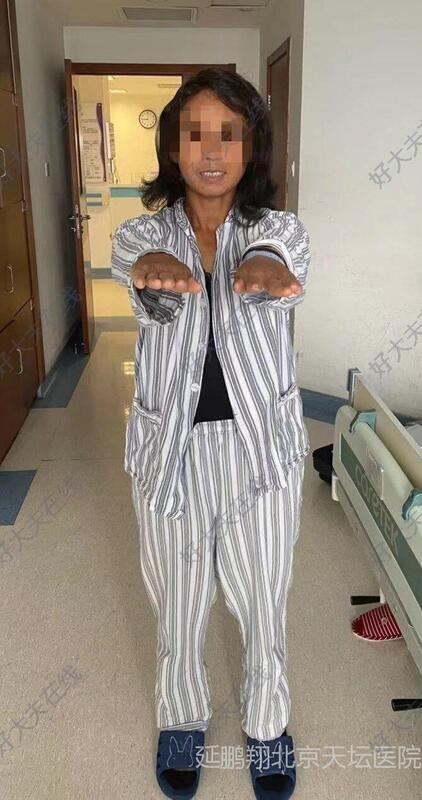

术后病人全麻苏醒顺利,生命体征平稳,四肢活动好。常规术后六小时复查头颅CT显示肿瘤消失。

术后病人恢复顺利,睡眠,进食,精神状态,行走均正常。常规复查核磁,显示肿瘤消失。

术后第七天病人伤口拆线,无红肿,无渗出,甲级愈合。病人高高兴兴出院回家。

伤口隐蔽在头发里,几乎看不到。

微创手术的优点:时间短,创伤轻,反应小,出血少,恢复快。附合当今发展理念和病人的需求。